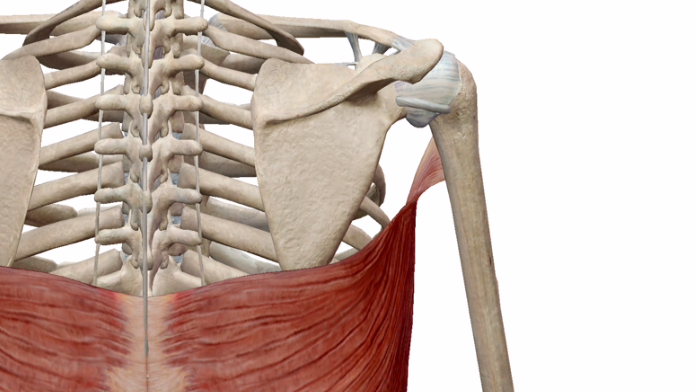

こいつのココが気になります。

この、腕に付く部分のねじれです。

別角度はこちら↓

ねじれてますね。

これ、なんでねじれているのでしょう?